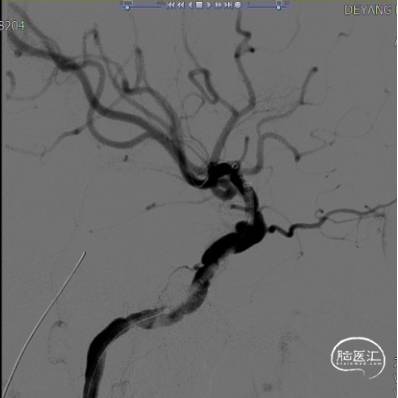

(A)

(B)

(C)

(D)

(E)

(F)

A:准备定位后打开Surpass Streamline头端于Catalyst 5。

B:缓慢回撤Catalyst 5,逐渐释放Surpass Streamline。

C:支架收尾。

D:Catalyst 5中间导管进行支架内按摩。

E:动脉瘤腔内可见造影剂滞留。

F:动脉瘤腔内可见造影剂滞留(另一角度)。

术后复查头部CT可见Surpass Streamline FD全程无狭窄,贴壁满意。患者无神经功能缺损表现,医嘱离院。